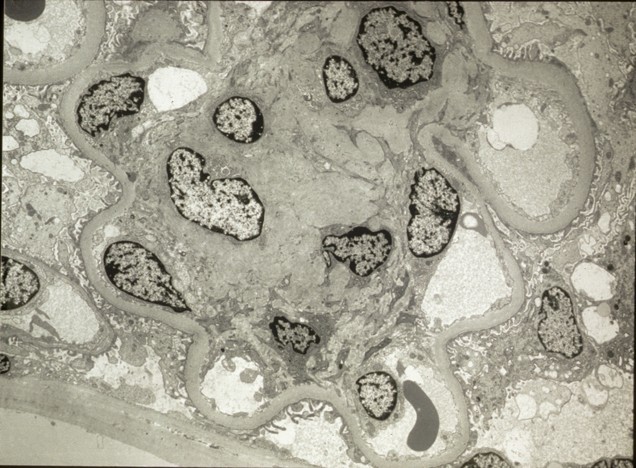

M.S. is a 3yr old boy who presents to the office with generalized edema and abdominal distention

UA – 3+protein, no RBCs

CXR – bilateral pleural effusions

Labs – Albumin 1.2 g/dL, total cholesterol 472 mg/dL, BUN 21 mg/dL, creatinine 1.2 mg/dL

Electron microscopy: below

What is the diagnosis and treatment?

Minimal Change disease:

“Nil” disease= Proteinuria with epithelial cell foot processes fusion

Most common cause of nephrotic syndrome in children